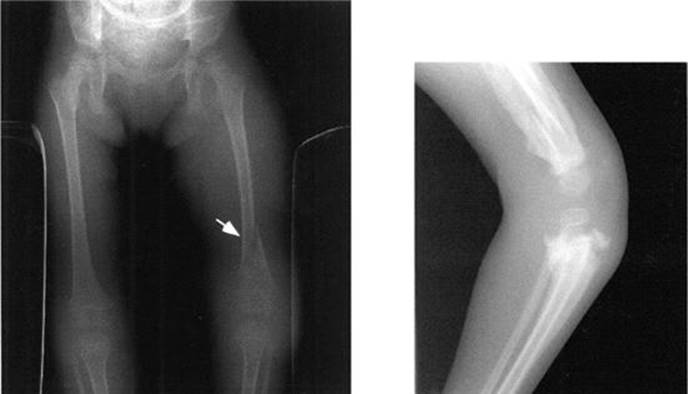

Spiral fractures of lower extremities in nonambulatory children (see Figure 6-1A and B).

FIGURE 6-1. A. Spiral fracture (arrow) of the femur in a nonambulatory child, consistent with nonaccidental trauma. B. Same child 2 months later. Note the exuberant callus formation at all the fracture sites in the femur and proximal tibia and fibula.